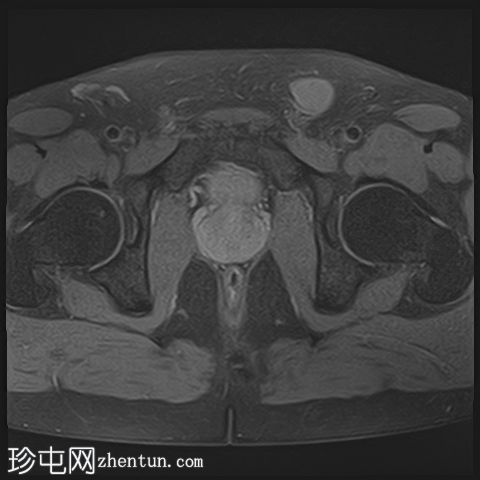

轴位

T1加权像

2.png

轴位T1加权像

脂肪抑制像

龟头可见不规则形状的软组织肿块,增强后明显强化,并伴有扩散受限。该肿块侵犯尿道海绵体,导致远端尿道狭窄和上游尿道扩张。

左侧腹股沟可见多个肿大的病理性淋巴结,右侧可见较小的非特异性淋巴结。